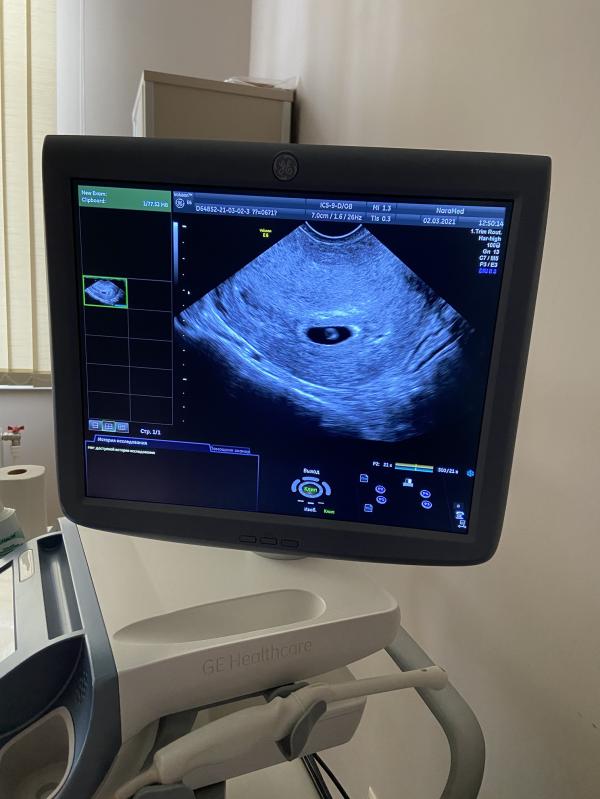

Всё хорошо!

Плодное яйцо на месте💜